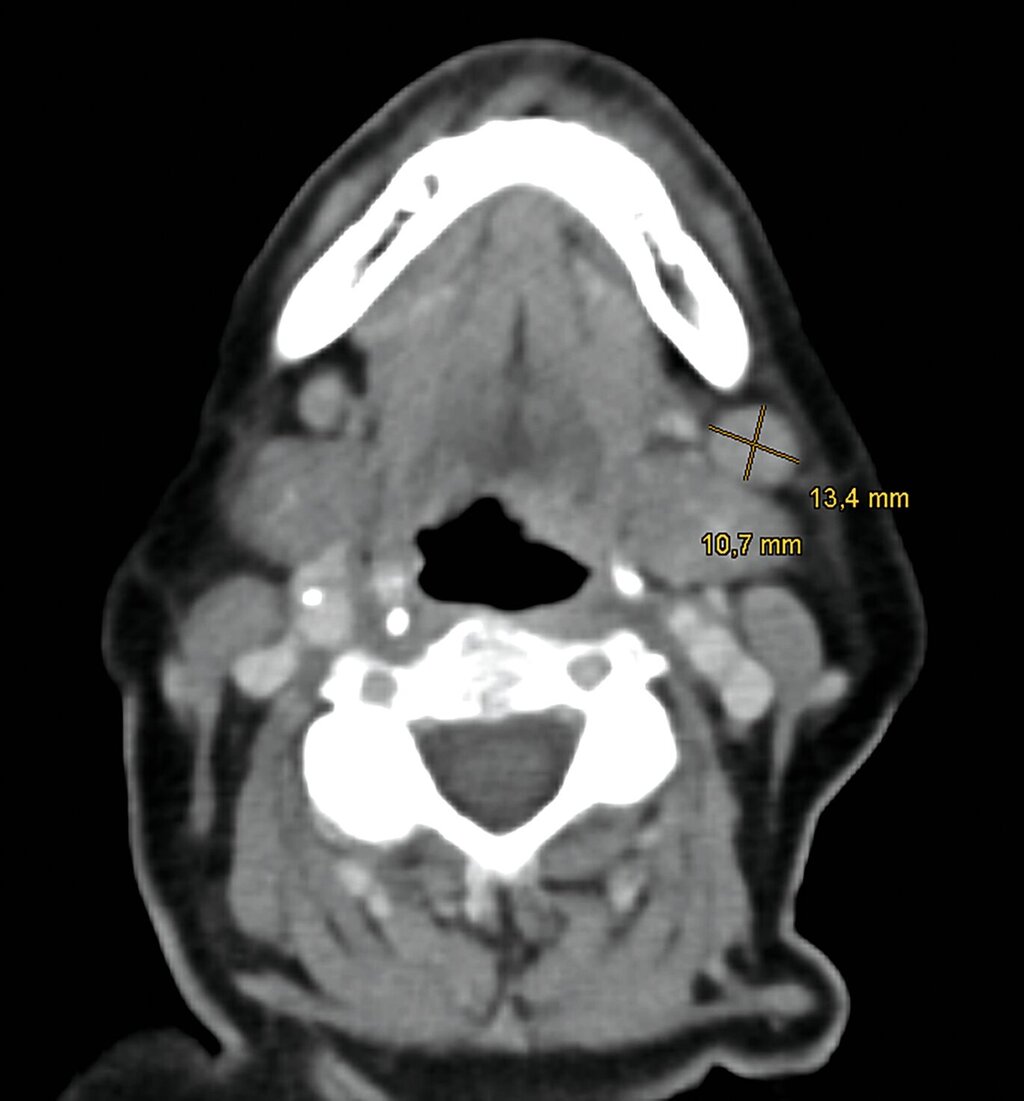

Es erfolgten eine Ausbreitungsdiagnostik mittels Ultraschall der zervikalen Lymphknoten, eine Computertomografie (CT) von Hals, Thorax und Abdomen sowie eine Magnetresonanztomografie (MRT) des Schädels. Radiologisch und sonografisch zeigten sich insbesondere in Level I A/B linksbetont suspekte Lymphknoten (Abbildung 3).